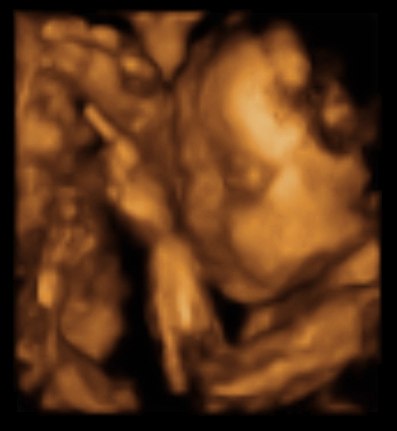

Har været til 3D scanning, hvilket var en fantastisk oplevelse...

Synes lige jeg ville dele nogle af billederne med jer....Så her har i lille Madicken